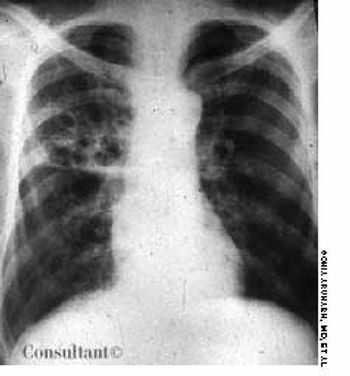

A 25-year-old man, who was an injection drug user, presented with a several-day history of dyspnea and fever. He complained of excessive malaise, fatigue, and weight loss but denied any hemoptysis. The examination of the lung revealed bilateral crackles in both lower zones.